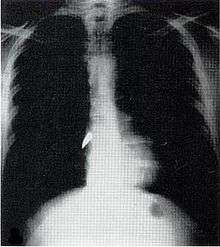

X-ray showing a bullet (white spot) in the heart

Most penetrating injuries are chest wounds and have a mortality rate (death rate) of under 10%.[11] Penetrating chest trauma can injure vital organs such as the heart and lungs and can interfere with breathing and circulation. Lung injuries that can be caused by penetrating trauma include pulmonary laceration (a cut or tear) pulmonary contusion (a bruise), hemothorax (an accumulation of blood in the chest cavity outside of the lung), pneumothorax (an accumulation of air in the chest cavity) and hemopneumothorax (accumulation of both blood and air). Sucking chest wounds and tension pneumothorax may result.

Penetrating trauma can also cause injuries to the heart and circulatory system. When the heart is punctured, it may bleed profusely into the chest cavity if the membrane around it (the pericardium) is significantly torn, or it may cause pericardial tamponade if the pericardium is not disrupted.[12] In pericardial tamponade, blood escapes from the heart but is trapped within the pericardium, so pressure builds up between the pericardium and the heart, compressing the latter and interfering with its pumping.[12] Fractures of the ribs commonly produce penetrating chest trauma when sharp bone ends pierce tissues.